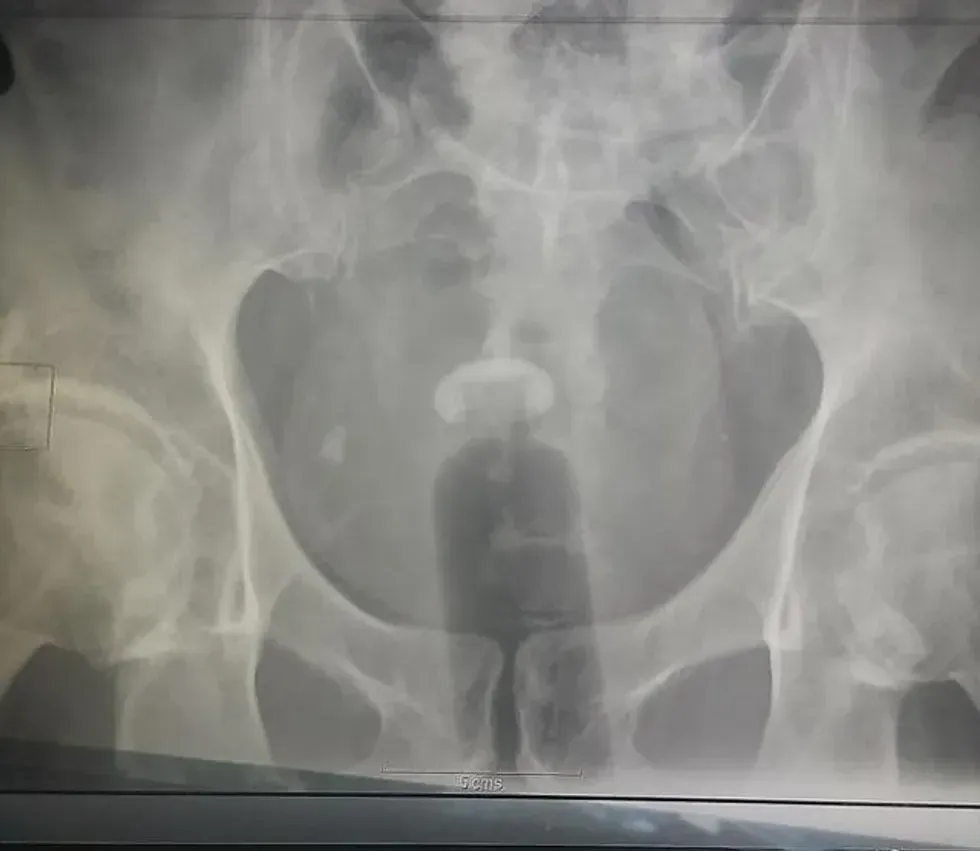

16. A key